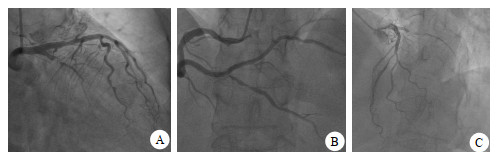

病例2,女,61岁。持续性心前区疼痛52 h,加重15 h,心电图提示:前壁、下壁ST-T改变(图 5)。cTnI 19.25 ng/mL,CK-MB 98.2 ng/mL(图 6),以非ST段抬高型心肌梗塞收住。评估后急诊PCI示罪犯血管OM 100%(图 7A),打通后置入2.25 mm×31.00 mm支架,PDA起始部95%狭窄(图 7B),FFR 0.78,LAD中段狭窄70%(图 7C),FFR 0.84(阴性),于PDA放置2.75 mm×29.00 mm支架,OCT测定支架远端膨胀不全,近端贴壁不良(图 8A),分别后扩球囊反复扩张,OCT再次检查无膨胀不全及贴壁不良现象(图 8B),FFR 0.92(图 8C),心肌酶趋势如图 6所示。

| A为OM 100%为罪犯血管;B为PDA起始部95%,FFR 0.78;C为LAD 75%,FFR 0.84 图 7 病例2的冠脉造影检查结果 |